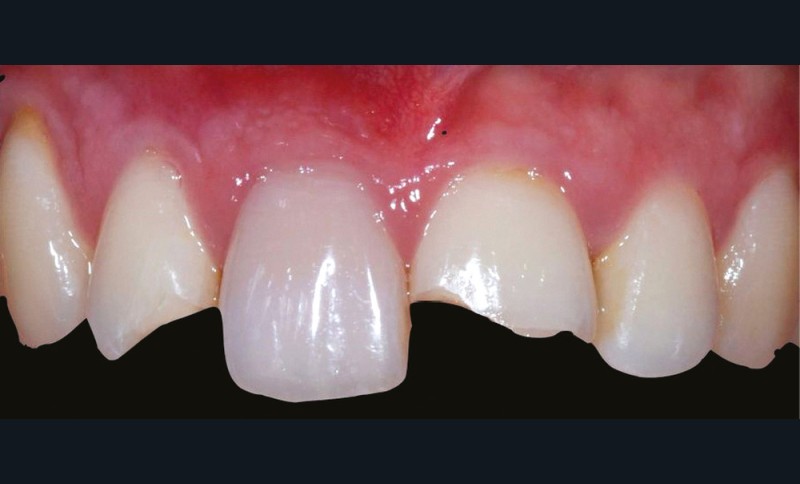

– le trauma, qui va donner une couleur plutôt rouge [4] (fig. 3) ;

– les soins conservateurs et endodontiques [5] (fig. 4 et 5).